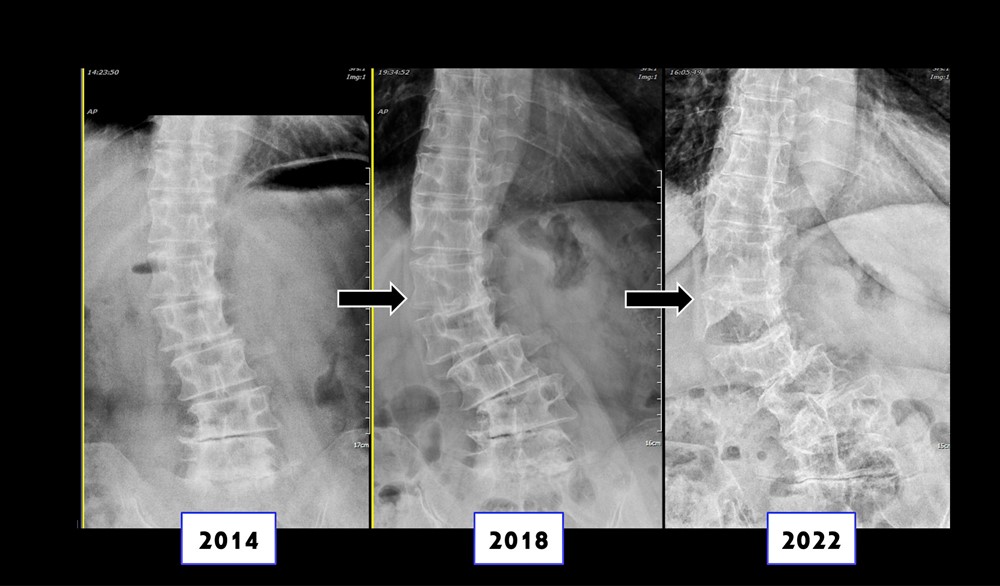

六十四歲女性於七年間側彎情況加劇、嚴重錯位。

接受手術治療後完全矯正。

另一位女性病人是六十四歲保母,初發現脊椎側彎時,角度還不嚴重。但因工作需要抱小孩和長時間站立,加上有扁平足和風濕免疫疾病,七年後,脊椎側彎角度已經惡化到整個脊椎骨都錯位。病人在多家醫院看診也都診斷需要手術,不過病人骨質不好,手術難度很高。最後,選擇了台中慈院微創脊椎關節中心。

張主任採用電腦導航前開加後開的手術,先從腹部矯正脊椎骨,再從背後固定支架。術後,病人脊椎側彎角度完全矯正回來,五天左右就出院。張主任指出,微創脊椎手術治療嚴重脊椎側彎具有多項優點,包括傷口小,破壞組織少,術後疼痛輕微,復原時間更短;有電腦導航輔助,精準矯正脊椎角度,減少手術風險;適用於骨質較差的病人。